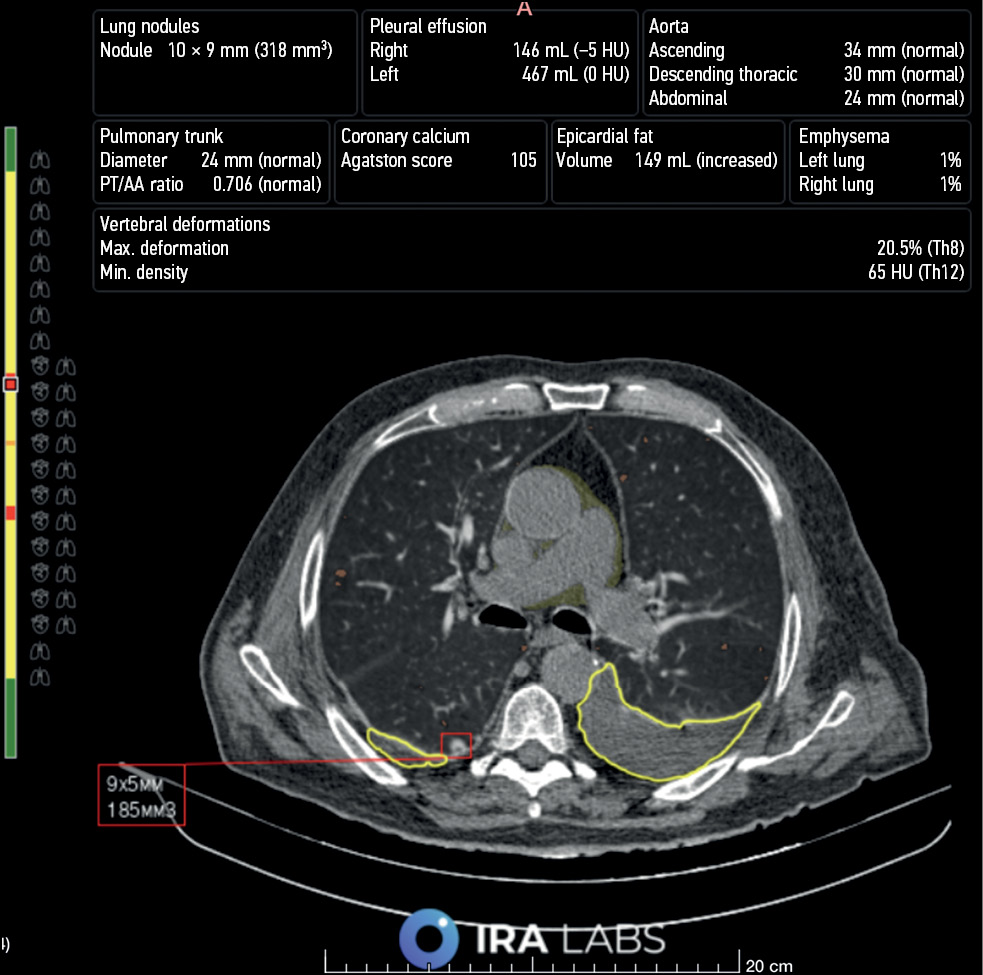

Fig. 6. An example of AI use. Patient B, 76 years old. A radiologist correctly identified bilateral hydrothorax and emphysematous changes but did not describe the lung nodule in the right lung. An AI algorithm revealed all three pathological findings: hydrothorax is highlighted with a yellow line, emphysematous changes are highlighted in orange, and the lung nodule is indicated by a red square.